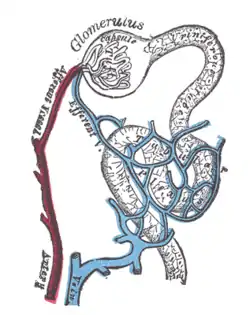

Distribution of blood vessels in cortex of kidney.

Distribution of blood vessels in cortex of kidney. Glomerulus.